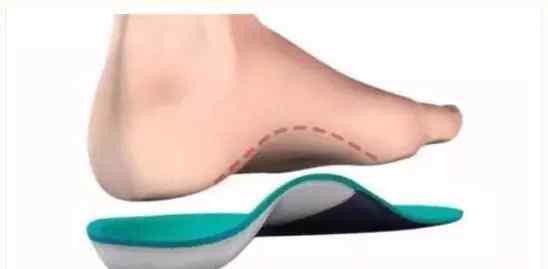

正常的足弓和足底筋膜的结构类似于弓和弓弦。负重站立时,足弓下压,弓弦绷紧,压力增大。持续的异常牵引刺激会导致弓弦止点无菌性炎症。

适当休息数周,调整行走方式,避免久站和长时间走路。若无禁忌,可口服布洛芬或双氯芬酸钠、塞来昔布等药物止痛。足底踩在啤酒瓶上滚动几分钟,每天至少2次,2-8周,缓解足弓疼痛。用鞋垫或足弓垫支撑足弓,缓解疼痛。可用一小块纱布垫在足心。